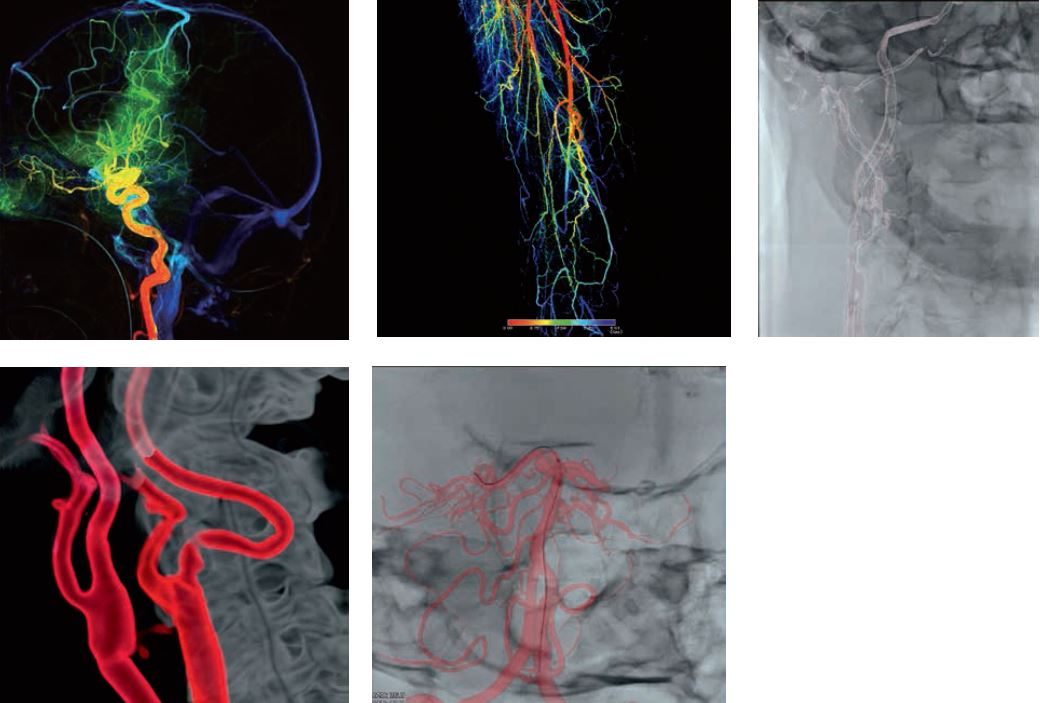

3. Численні програми для кількісного аналізу зображень, програми для покращення візуалізації стентів, програми для аналізу дозового навантаження, функції отримання, аналізу та накладання 3D-зображень, програми для оцінки перфузії судин та широкі можливості постробробки – прокриють усі, навіть найвибагливіші потреби.